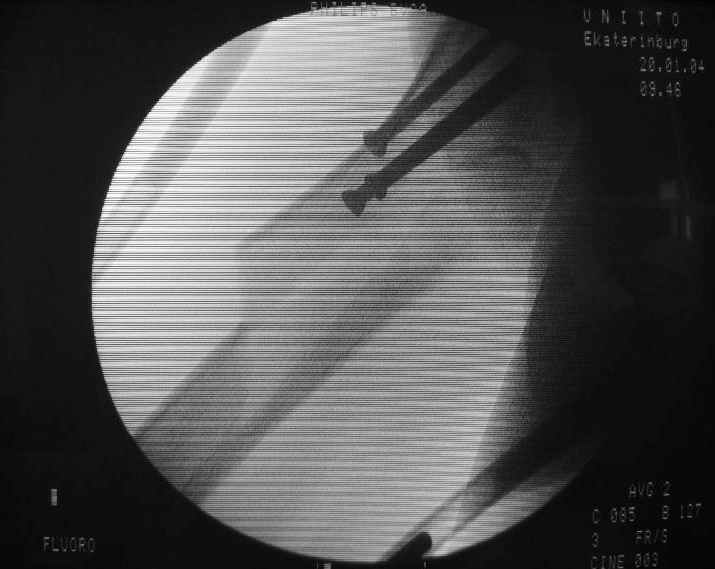

Еще одна боковая проекция. На сегодня назначен закрытый интрамедуллярный остеосинтез. Реконструкционного гвоздя для этой больной не нашлось, придется делать обычным.

Another lateral view. A closed nailing is scheduled for today. No reconstuction nail is available so a usual one is planned.